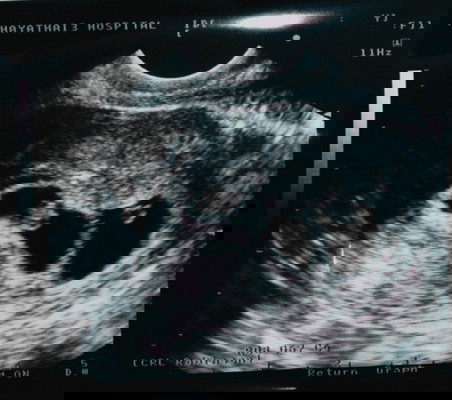

ถุงตั้งครรภ์ไม่กลม

แม่บ้านไหนถุงตั้งครรภ์ไม่กลมบ้างคะ. บ้านนี้กังวลมากที่สุดเลยคะ. ค่อนข้างจะจิตตกส่ะแล้ว 6วีค2+ 🥺🥺🥺 #ขอบคุณล่วงหน้านะคะ #ใครมีประสบการณ์ 😞😞😞😞

ของเราตอนซาวด์ครั้งแรกก็ถุงไม่กลมค่ะ ตอนนี้ 15+ แล้ว แม่ได้ลูกแฝดใช่มั้ยคะ เห็นมี 2 ถุง 😆😆

อย่าคิดมากคะแม่ ปรึกษาหมอได้ พักผ่อนๆ ถ้ามี2ถุงแล้วไม่กลมก่มีสิทธิ์เพราะถุงจะทับกัน

เเฝดเหมือนกันเลยค่า เกือบจะกลมอยู่ค่ะ55 ตอนนี้เเฝดๆได้13วีคเเล้วค่า รูปตอน8วีคค่ะ

บ้านนี้ก็ถุงตั้งครรภ์ไม่กลม ถุงจะเปลี่ยนรูปร่างตามตัวเด็กอย่ากังวลค่ะ